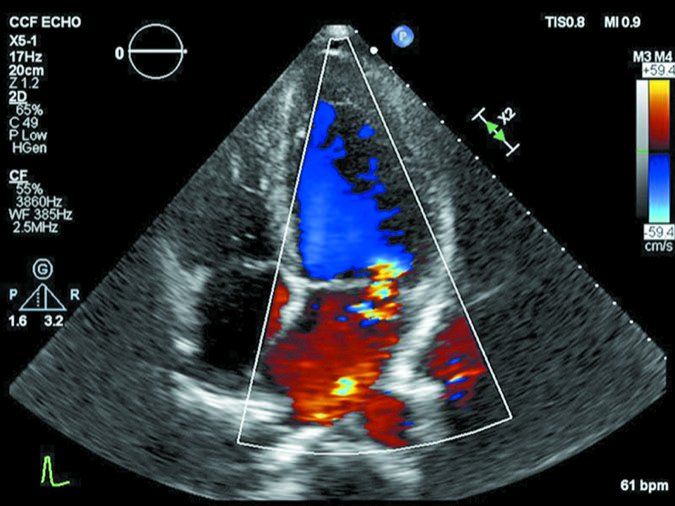

Most people are familiar with ultrasound as the technology used to monitor unborn babies during pregnancy. When ultrasound is used to look inside a beating heart from outside the body, it is called echocardiography. The technology produces images from sound waves bounced off theheart.